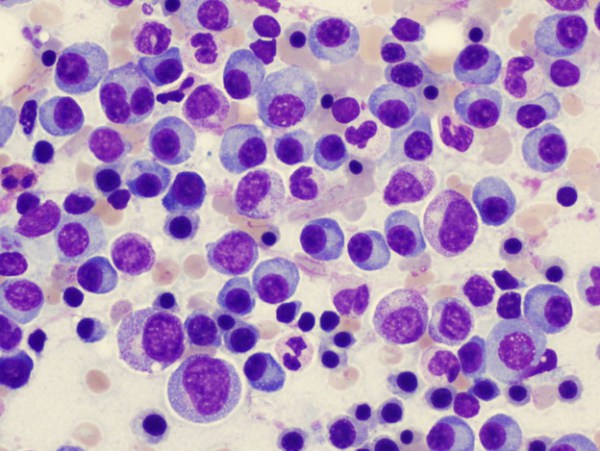

Νέα θεραπεία για το πολλαπλό μυέλωμα

Η Amgen ανακοίνωσε ότι η Ευρωπαϊκή Επιτροπή ενέκρινε την επέκταση της ένδειξης για τη δενοσουμάμπη, για την πρόληψη των σκελετικών συμβαμάτων σε ενήλικες με προχωρημένου σταδίου κακοήθειες που εμπλέκουν τα οστά. Η ένδειξη πλέον καλύπτει ασθενείς με οστικές μεταστάσεις από συμπαγείς όγκους καθώς και...